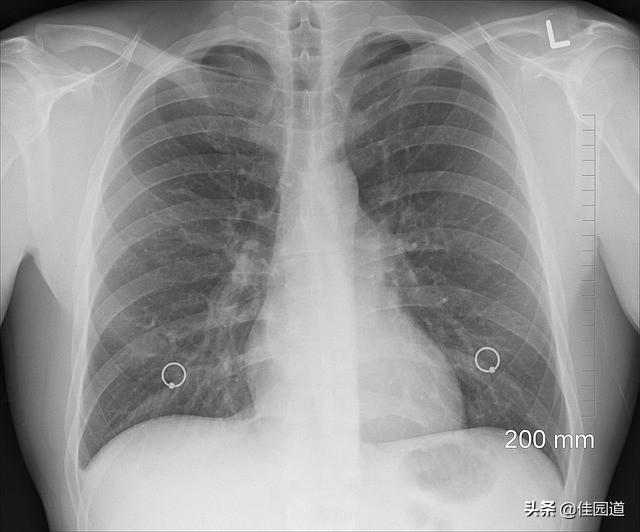

- Le scanner thoracique est actuellement la méthode de dépistage du cancer du poumon la plus efficace. Si l'examen par scanner thoracique révèle des nodules pulmonaires avec un signe lobaire, un signe de bavure, un signe vacuolaire, une image bronchique aérienne, une artère trophoblastique tumorale, une coupure vasculaire et un signe d'amas, une dépression pleurale ou un signe de traction, une cavité excentrique, une lésion ressemblant à du verre dépoli, une masse hilaire et d'autres signaux d'imagerie, le cancer du poumon est fondamentalement confirmé.

Étant donné que de nombreux patients atteints d'un cancer du poumon à un stade précoce ne présentent pas de symptômes évidents et les négligent, ils sont souvent traités à l'aveuglette comme des maladies pulmonaires courantes et la détection et le traitement précoces sont retardés. Par conséquent, afin de détecter le cancer du poumon à un stade précoce, il est nécessaire de prêter attention à l'examen physique et de se rendre à l'hôpital pour une radiographie pulmonaire, un scanner thoracique, des tests de laboratoire sur les expectorations, une bronchoscopie et d'autres examens pertinents afin d'exclure et de diagnostiquer le cancer du poumon à temps lorsque les symptômes suspects suivants se manifestent. Les personnes qui fument depuis longtemps, qui ont été exposées à des substances radioactives, à l'amiante, au gaz et qui souffrent de maladies respiratoires chroniques et de tuberculose doivent être particulièrement vigilantes.